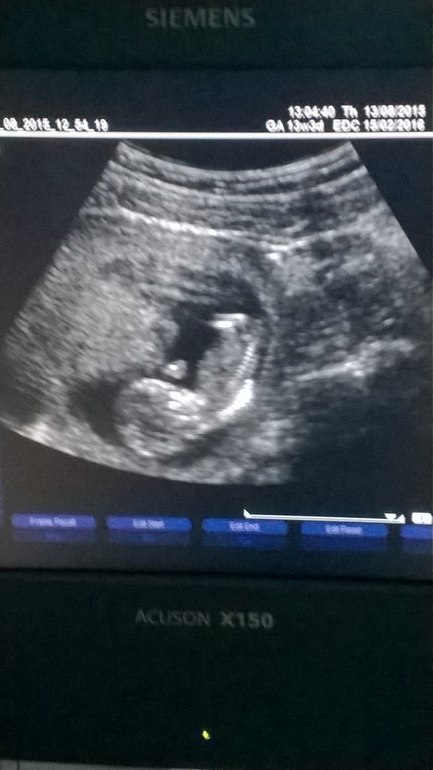

Вчера впервые была на УЗИ....сколько волнения перед первым свиданием...И вот....Лежу на кушетке.....смотрю в зеркало....и вижу в мониторе то маленькое чудо,что живет внутри меня....Боже...сколько было эмоций...Наконец то сказали что все хорошо...это настоящее счастье-слышать,что малыш развивается как надо)Пол пока не определили....жду с нетерпением второго свидания!И я снова увижу тебя,моя кроха....